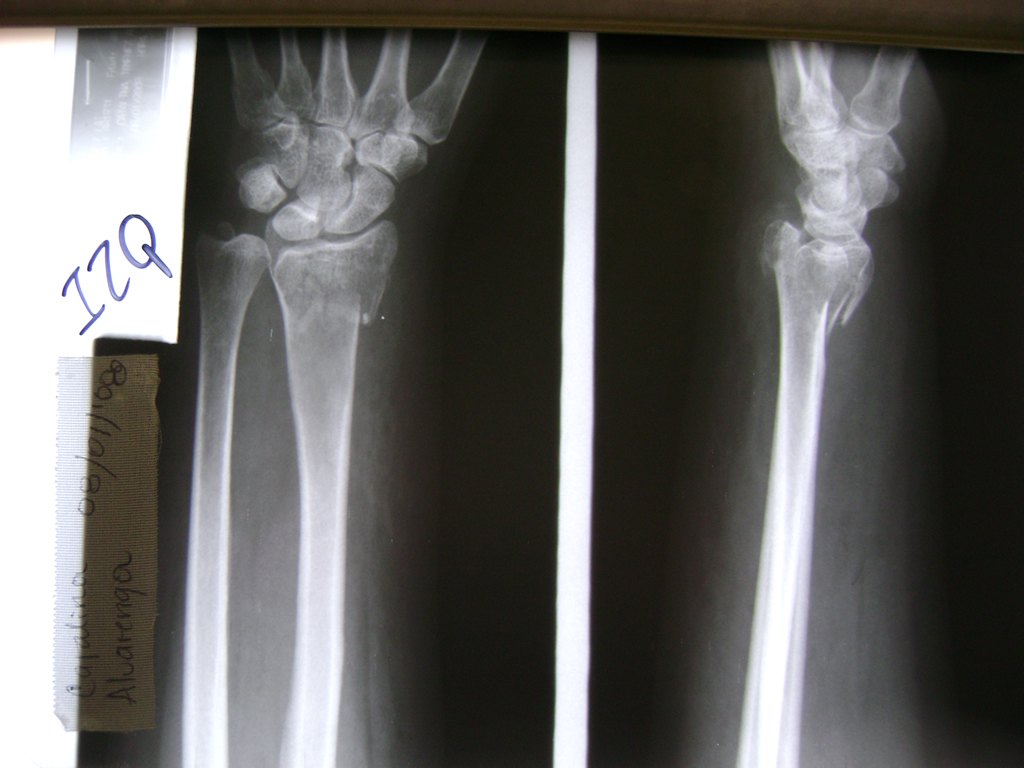

Cirugía de Muñeca y Mano

Los procedimientos más comunes en cirugía de la mano son aquellos destinados a reparar traumatismos, incluyendo lesiones de tendones, nervios, vasos sanguíneos, y articulaciones; huesos fracturados; y quemaduras, cortes, y otros daños de la piel.